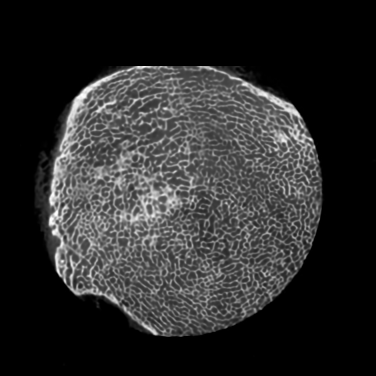

Figure 4: Visual comparsion of SRCT Case 111 from the Tibia dataset. The restored bony structures are shown in the red and yellow boxes in Fig. 5. The display window is [-900, 2000] HU.

Figure 5: Zoomed regions of interest (ROIs) marked by the red rectangle in Fig. 4. The restored image with GAN-CIRCLE reveals subtle structures better than the other variations of the proposed neural network, especially in the marked regions. The display window is [-900, 2000] HU.

III-D Experimental Results with the Tibia Dataset

We evaluated the proposed algorithms against the state-of-the-art algorithms on the tibia dataset. We present typical results in Fig. 4. It is observed that BM3D can effectively remove the noise, but it over-smoothens the noisy LR images. Then, the interpolation-based methods (NN+, Bilinear+, Bicubic+, Lanczos+) yield noticeable artifacts caused by partial aliasing. On the other hand, the DL-based methods suppress such artifacts effectively. It can be seen that our proposed GAN-CIRCLE recovers more fine subtle details and captures more anatomical information in Fig. 5. It is worth mentioning that Fig. 4 shows that there are severe distortions of the original images but SRGAN generates compelling results in Figs. 6-8, which indicate VGG network is a task-specific network which can generate images with excellent image quality. We argue that the possible reason is that the VGG network [68] is a pre-trained CNN-based network based on natural images with structural characteristic correlated with the content of medical images [80]. Fig. 5 presents that the proposed GAN-CIRCLEs can predict images with shaper boundaries and richer textures than GAN-CIRCLE, and GAN-CIRCLEu which learns additional anatomical information from the unpaired samples. The quantitative results are in Table II. The results demonstrate that the G-Forward achieves the highest scores using the evaluation metrics, PSNR and SSIM, which outperforms all other methods. However, it has been pointed out in [81, 82] that high PSNR and SSIM values cannot guarantee a visually favorable result. Non-GAN based methods (FSRCNN, ESPCN, LapSRN) may fail to recover some fine structure for diagnostic evaluation, such as shown by zoomed boxes in Fig. 5. Quantitatively, GAN-CIRCLE achieves the second best values in terms of SSIM and IFC. It has been pointed out in [83] that IFC value is correlated well with the human perception of SR images. Our GAN-CIRCLEs obtained comparable results qualitatively and quantitatively. Table II shows that the proposed semi-supervised method performs similarly compared to the fully supervised methods on the tibia dataset. In general, our proposed GAN-CIRCLE can generate more pleasant results with sharper image contents.